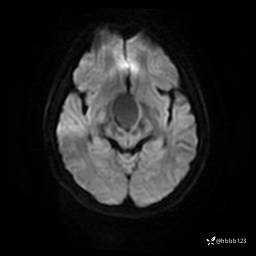

DWI: